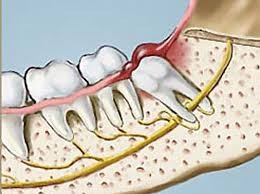

È sempre indicata in presenza di denti sovrannumerari. Nel caso dei "denti del giudizio " occorre intervenire quando compaiono dolori, ascessi, o per prevenire lesioni al settimo dente; in assenza di tali indicazioni si può attendere (meglio non svegliare il "can che dorme"). L'intervento può essere molto indaginoso, soprattutto nel caso degli inferiori che abbiano le radici in vicinanza del nervo mandibolare.